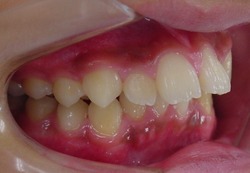

初診時 12歳3ヶ月 女子

終了時 15歳1カ月

ブラケット(矯正装置)を歯に装着して歯並びを改善します。

MEAW(マルチループ)を利用して咬み合わせの高さや咬合平面を変える事で下顎を前方に移動して上顎前突(出っ歯)を改善していきます。

本来、第一小臼歯を4本抜歯しなければならない状態でしたがMEAW(マルチループ)を利用する事で咬合平面を変え、咬合の高さを変える事で下顎骨を回転させながら前方に移動させて上顎前突(出っ歯)を改善する事ができました。

ただし、ある程度の年齢になると顎の関節が固まり治療出来なくなることもあります。